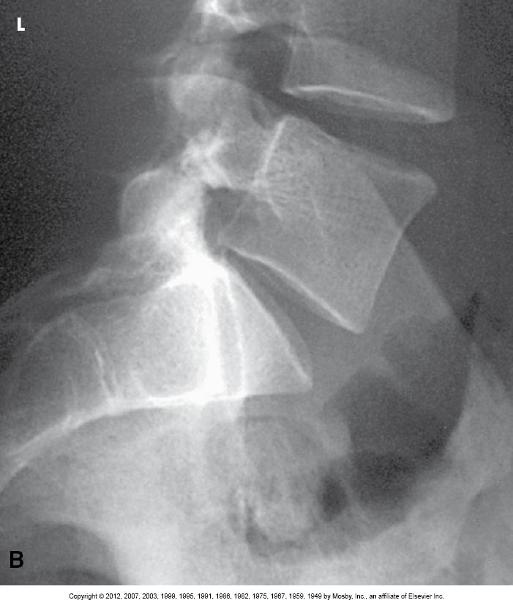

1) Place the patient in a true

lateral position (usually left)

2) Flex the knees and hips to a

comfortable position

3) Center the image receptor to the median

coronal plane and level of the iliac crests for a 14 x 17, 1½"

above the crest for an 11 x 14

4) If necessary, place a support

under the lower thorax and waist

5) Shield patient

6)

Suspend respiration after full exhalation

Central Ray

•

Perpendicular to the level of the iliac crests (L4) for a 14 x 17 and

median coronal plane

Structures Shown

• All five lumbar

vertebrae

• Open intervertebral foramina

**NOTE: To improve

image quality, a lead strip can be placed on the table behind the

patient's back to attenuate scatter radiation**

Lateral of the lumbar spine (R or L)